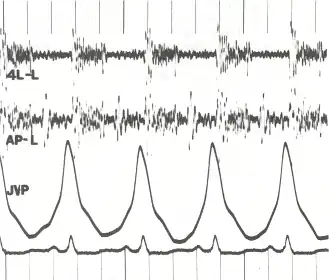

Phonocardiogram and jugular venous pulse tracing from a middle-aged man with pulmonary hypertension (pulmonary artery pressure 70 mm Hg) caused by cardiomyopathy. The jugular venous pulse tracing demonstrates a prominent a wave without a c or v wave being observed. The phonocardiograms (fourth left interspace and cardiac apex) show a murmur of tricuspid insufficiency and ventricular and atrial gallops.[1]